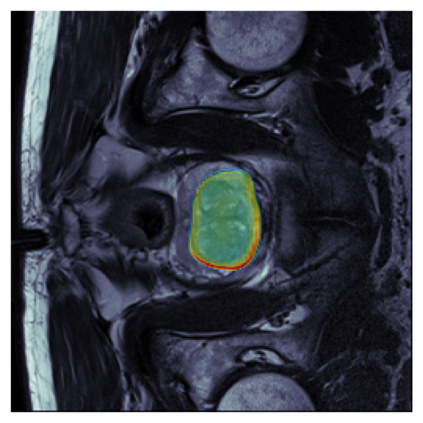

The sigmoid activation is the standard output activation function in binary classification and segmentation with neural networks. Still, there exist a variety of other potential output activation functions, which may lead to improved results in medical image segmentation. In this work, we consider how the asymptotic behavior of different output activation and loss functions affects the prediction probabilities and the corresponding segmentation errors. For cross entropy, we show that a faster rate of change of the activation function correlates with better predictions, while a slower rate of change can improve the calibration of probabilities. For dice loss, we found that the arctangent activation function is superior to the sigmoid function. Furthermore, we provide a test space for arbitrary output activation functions in the area of medical image segmentation. We tested seven activation functions in combination with three loss functions on four different medical image segmentation tasks to provide a classification of which function is best suited in this application scenario.